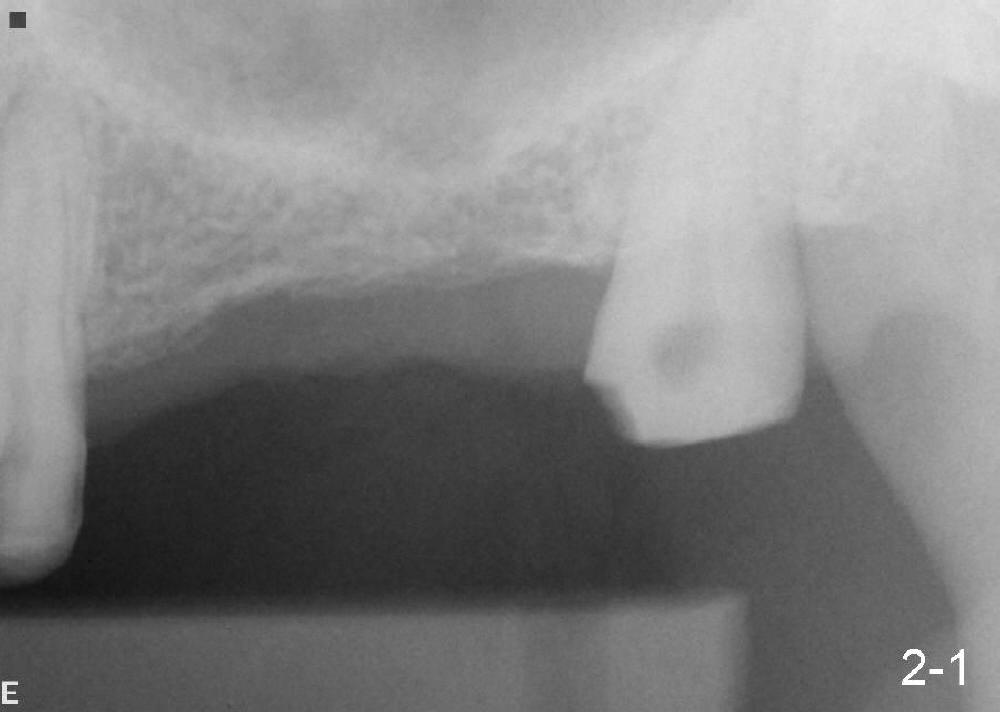

沐旭升医师送来两例植骨病例:第一例使用金属网(图一);第二例上颌骨头高度3.4 mm (CT 显示),上颌窦提高术植骨(侧面进路),同期植牙(图二)。打开每张图看评论。

Case1 is bone graft with metal mesh. Case 2 is bone graft with sinus lift through window, since the  existing bone only has 3.4 mm in the CT film (英文部分由沐医生提供).